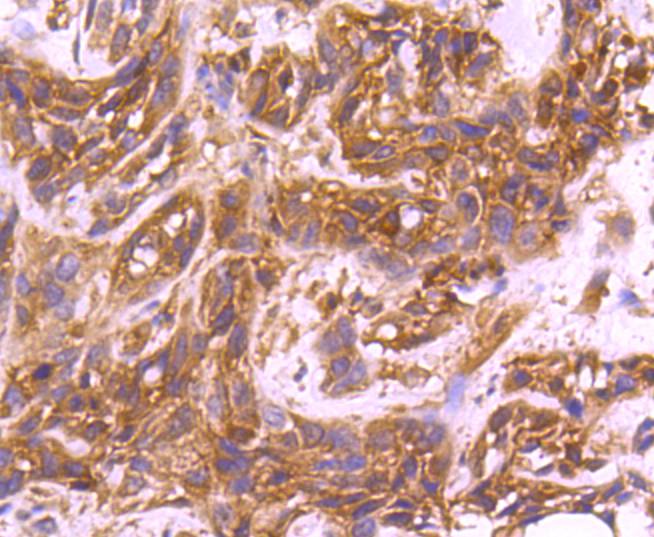

Immunohistochemical analysis of paraffin-embedded human breast carcinoma tissue using anti-CDC42 antibody. Counter stained with hematoxylin.